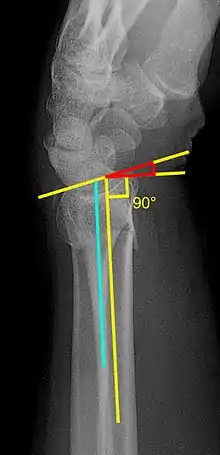

Various kinds of information can be obtained from X-rays of the wrist:[5]

Lateral view

- Carpal malalignment - A line is drawn along the long axis of the capitate bone and another line is drawn along the long axis of the radius. If the carpal bones are aligned, both lines will intersect within the carpal bones. If the carpal bones are not aligned, both lines will intersect outside the carpal bones. Carpal malignment is frequently associated with dorsal or volar tilt of the radius and will have poor grip strength and poor forearm rotation.[5]

- Tear drop angle - It is the angle between the line that pass through the central axis of the volar rim of the lunate facet of the radius and the line that pass through the long axis of the radius. Tear drop angle less than 45 degrees indicates displacement of lunate facet.[5]

- Antero-posterior distance (AP distance) - Seen on lateral X-ray, it is the distance between the dorsal and volar rim of the lunate facet of the radius. The usual distance is 19 mm.[5] Increased AP distance indicates the lunate facet fracture.[8]

- Volar or dorsal tilt - A line is drawn joining the most distal ends of the volar and dorsal side of the radius. Another line perpendicular to the longitudinal axis of the radius is drawn. The angle between the two lines is the angle of volar or dorsal tilt of the wrist. Measurement of volar or dorsal tilt should be made in true lateral view of the wrist because pronation of the forearm reduces the volar tilt and supination increases it. When dorsal tilt is more than 11 degrees, it is associated with loss of grip strength and loss of wrist flexion.[5]

Posteroanterior view

- Radial inclination - It is the angle between a line drawn from the radial styloid to the medial end of the articular surface of the radius and a line drawn perpendicular to the long axis of the radius. Loss of radial inclination is associated with loss of grip strength.[5]

- Radial length - It is the vertical distance in millimetres between a line tangential to the articular surface of the ulna and a tangential line drawn at the most distal point of radius (radial styloid). Shortening of radial length more than 4mm is associated with wrist pain.[5]

- Ulnar variance - It is the vertical distance between a horizontal line parallel to the articular surface of the radius and another horizontal line drawn parallel to the articular surface of the ulnar head. Positive ulnar variance (ulna appears longer than radius) disturbs the integrity of triangular fibrocartilage complex and is associated with loss of grip strength and wrist pain.[5]